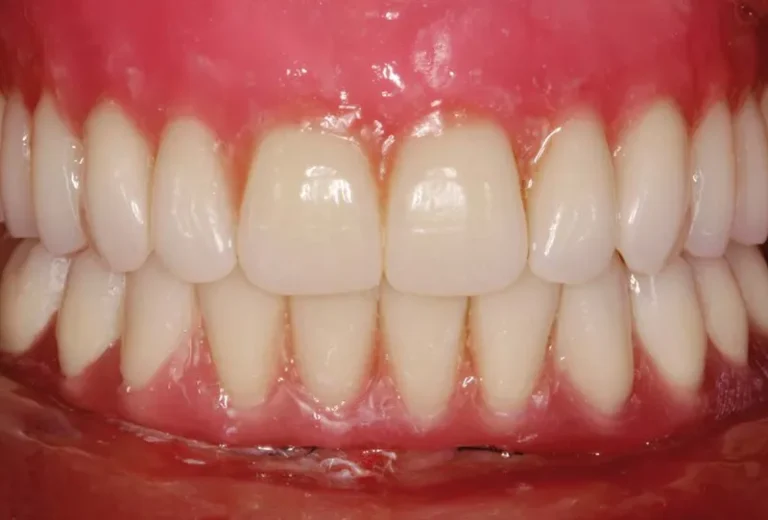

Mantener unas encías saludables es fundamental cuando tienes implantes dentales, ya que la longevidad y el éxito de estos dependen directamente de la salud del tejido gingival que los rodea. La higiene adecuada, el uso de herramientas específicas como cepillos interdentales y una técnica correcta de limpieza son esenciales para prevenir la periimplantitis y otras…

La elección entre implantes dentales y dentaduras removibles es una decisión importante que afecta directamente a nuestra calidad de vida. Los implantes dentales ofrecen una solución permanente que imita la función y apariencia de los dientes naturales, mientras que las dentaduras removibles son una opción más económica y menos invasiva. Cada alternativa tiene sus propias…